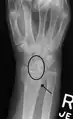

X-ray images indicate scapholunate ligament instability when the scapholunate distance is more than 3 mm, which is called scapholunate dissociation.[7] A static scapholunate instability is generally readily visible, but a dynamic scapholunate instability can only be seen radiographically in certain wrist positions or under certain loading conditions, such as when clenching the wrist, or loading the wrist in ulnar deviation.[6]

Dynamic instability: Increased scapholunate distance (between yellow lines) upon ulnar deviation of the wrist, but not otherwise.

Dynamic scapholunate instability visible upon clenching the wrist